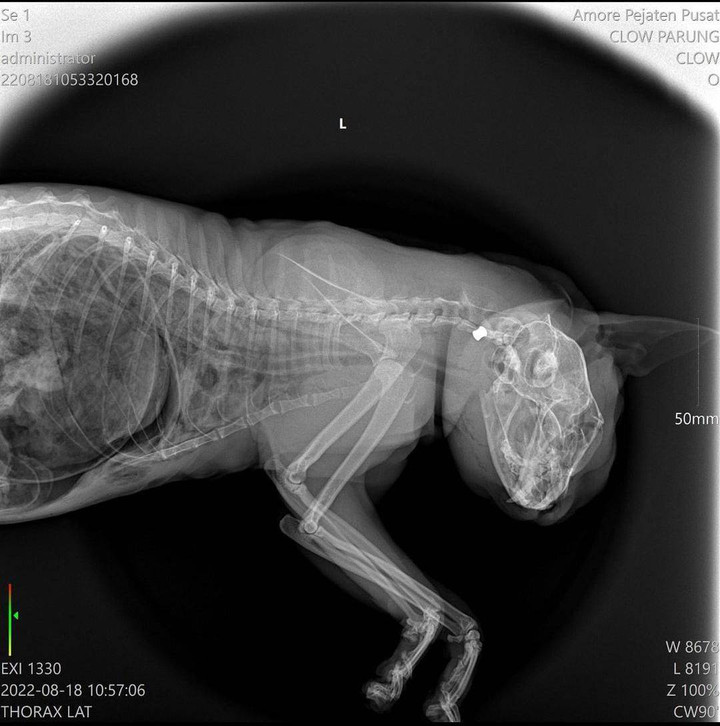

Kucing malang itu ditemukan oleh pecinta binatang dari Rumah Singgah Clow Bandung. Dari enam kucing yang ditemukan, empat ekor di antaranya mati akibat ditembak. Sementara dua ekor lainnya terluka parah. Kucing yang terluka saat ini dirawat di sebuah klinik hewan di Jakarta.